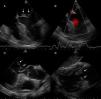

Ecocardiograma transesofágico. A y B. Vista medio esofágica de 4 cámaras (modificada), en las que se observan imágenes ecogénicas en la superficie auricular de ambas valvas de la válvula mitral, de gran tamaño, de bordes irregulares, sésiles, en festones A2 y P2 (flechas), que con doppler color permite observar insuficiencia valvular leve. C. Vista medio esofágica de eje largo de la válvula aórtica (modificada), donde se observan ambas vegetaciones adosadas a la superficie auricular de las valvas de la válvula mitral (flechas). D. Vista transgástrica de 2 cámaras. Se observan vegetaciones en la superficie auricular de las valvas de la válvula mitral (flechas).

Caso clínicoPaciente mujer de 28 años de edad, quien presentó 3 semanas antes de su ingreso, disnea a moderados esfuerzos que progresó a ortopnea. Una semana antes de su ingreso presentó epigastralgia, la cual no se calmó a pesar de diversos tratamientos indicados en centros de salud de su localidad, por lo cual fue trasladada al Servicio de Emergencias del Hospital Universitario de Los Andes. Tiene como antecedentes LES y SAF diagnosticado a los 15 años de edad, sin tratamiento en el momento de la evaluación, por abandono voluntario de la paciente. Presentaba una herida traumática en la pierna izquierda, la cual ameritó injerto de piel en el año 2005 y que, al momento de su ingreso, se encontró sobreinfectada. El servicio tratante solicitó valoración por cardiología, y se realizó ecocardiograma transtorácico (fig. 1), en el cual se observó engrosamiento de las porciones distales de ambas valvas de la válvula mitral, que generaba imagen de bordes irregulares y condicionaba a insuficiencia leve. Se solicitó hemocultivo, el cual resultó negativo hasta 7 días después de la incubación, y se realizó ecocardiograma transesofágico (fig. 2), en el cual se observaron imágenes ecogénicas, fijas, de bordes irregulares, adosadas a la superficie auricular de la valva anterior y posterior de la válvula mitral, de 14×9mm y 8×5mm respectivamente. Se solicitó un nuevo hemocultivo, el cual resultó nuevamente negativo. Además de ello la proteína C reactiva y la velocidad de sedimentación globular se encontraban dentro de límites normales, por lo cual no se inició antibioticoterapia. La paciente fue valorada por el servicio de reumatología, quienes determinaron que se encontraba con actividad lúpica e indicaron tratamiento inmunosupresor. Ante todos estos hallazgos clínicos y paraclínicos determinamos que las vegetaciones observadas en la paciente no eran debido a infección bacteriana, sino que concordaban con el diagnóstico de ELS.

En el ecocardiograma se pueden observar masas valvulares o vegetaciones, y engrosamiento valvular. Las masas pueden variar de forma y tamaño, generalmente más de 2mm de diámetro, con bordes que usualmente son irregulares, adheridas firmemente a la superficie valvular auricular o ventricular, sin exhibir movimientos independientes. Las válvulas que se afectan con mayor frecuencia son las del lado izquierdo. Cuando la válvula mitral se encuentra afectada, las vegetaciones se pueden extender al aparato subvalvular y al endocardio adyacente a la valva6. En este caso las masas sobrepasaban los 5mm, y se encontraban sésiles en la superficie auricular de la válvula mitral, sin extenderse al aparato subvalvular, y como se vio en el ecocardiograma transesofágico había insuficiencia mitral leve.